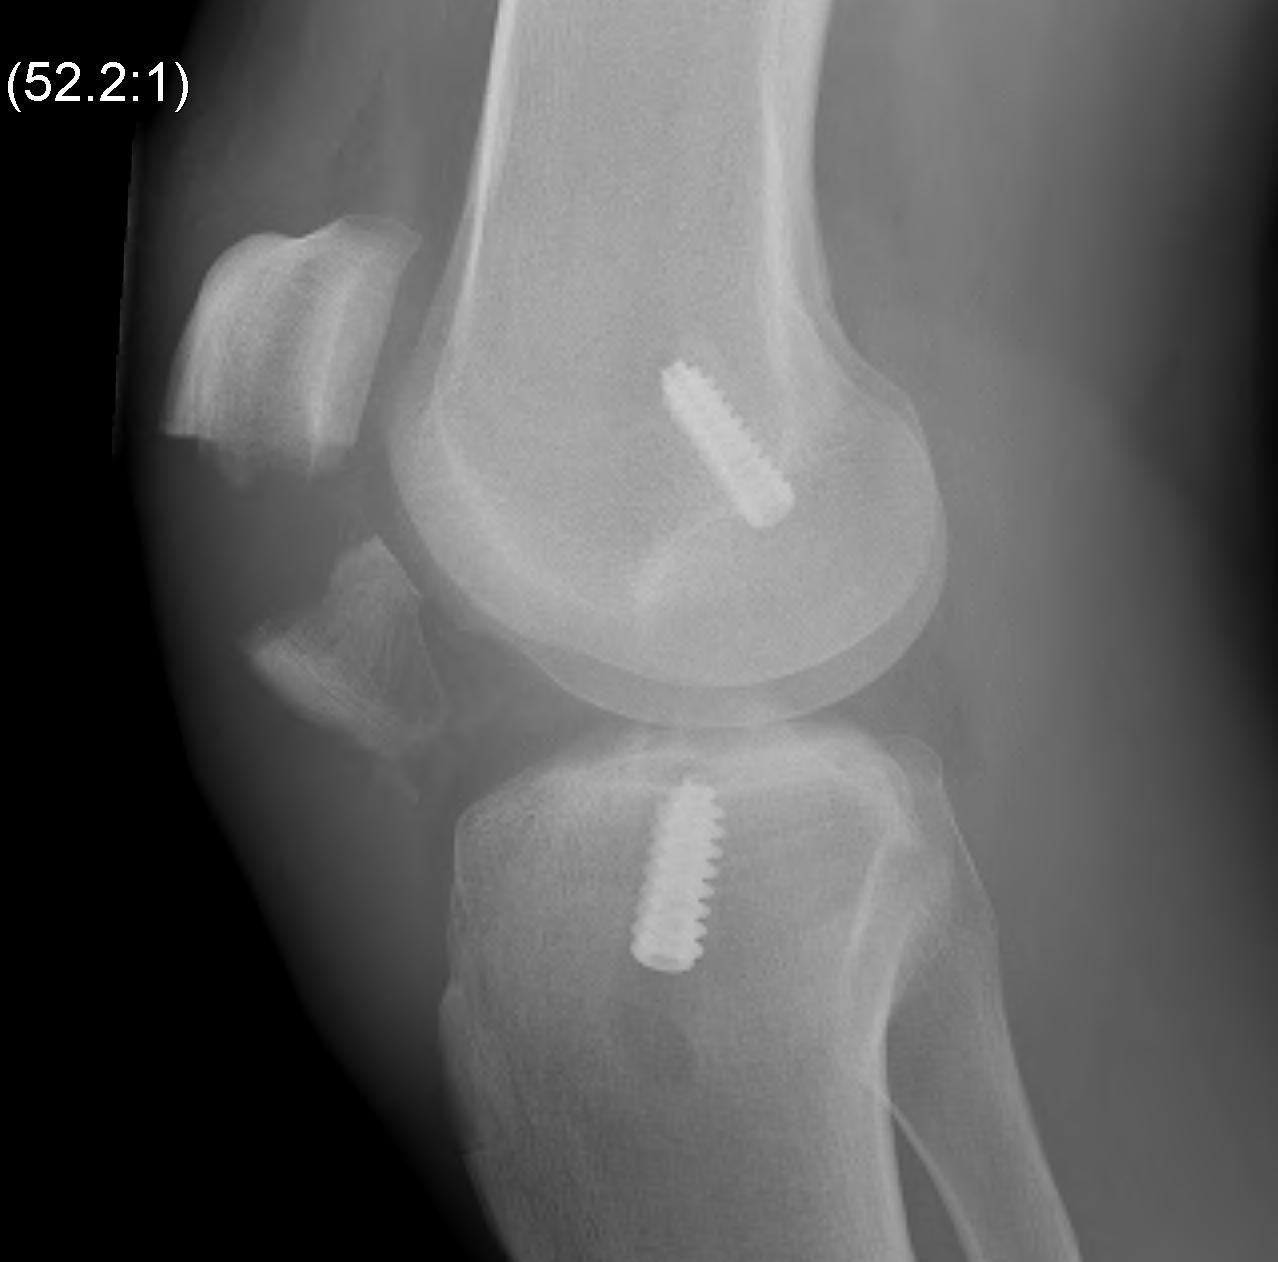

2. X-ray assessment

Lateral x-ray

Femoral tunnel

- intersection of line posterior femoral cortex and Blumensaat's line

Tibial tunnel

- posterior to Blumensaat's line in full extension

- parallel to Blumensaat's line

Pinczewski JBJS Br 2008

- 200 patients followed up over 7 years

1. Posterior femoral tunnel placement

- 86% along Blumensaat's line

2. Anterior tibia tunnel placement

- 48% along tibial plateau

- parallel to Blumensaat's